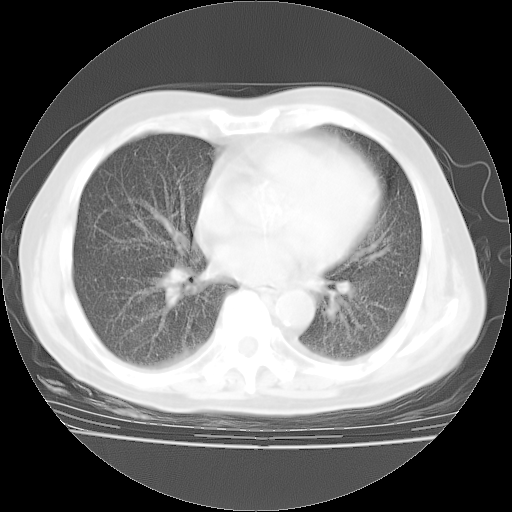

轻微咳嗽,无痰,(体温正常时)R20次/分,P75次/分,双肺底、腋下可闻及少量捻发音。下肢轻度浮肿。

增加治疗:异烟肼、利福平、乙胺丁醇,静滴左氧氟沙星、参麦注射液。甲强龙从80mg暂减为40mg。